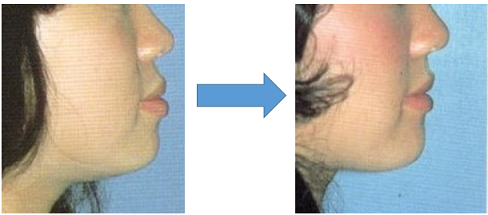

今回はいつも説明で使用している第5版 歯科矯正学 p238 図18-19抜粋

上下顎前突の症例について説明していきたいと思います。

上下顎前突・矯正前 矯正後(上下第一小臼歯を4本抜歯)

矯正前 矯正後

第5版 歯科矯正学 p284図18-20抜粋

上下顎前突で開咬状態に異常がある症例でも前歯部や顔貌の変化は見た目にはこんなものです。